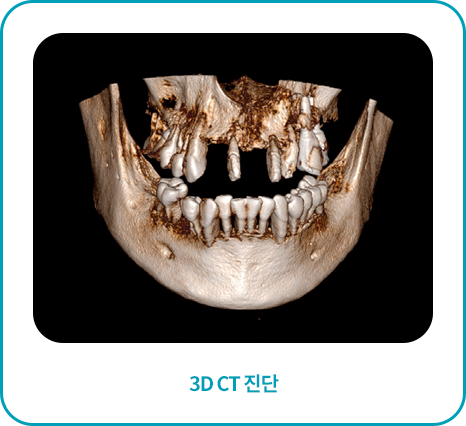

3D CT촬영으로 x-ray및 육안 진단만으로는 보이지 않는 뼈 조직의 상태,

신경의 위치까지 3차원 정밀 진단이 가능하여 보다 안전한 임플란트 수술로 성공률이 높습니다.

3D CT,구강스캐너를 이용한

정밀진단

육안으로 확인이 어려운 해부학적인 구조물까지

면밀히 검진한 결과를 토대로 각 환자에 맞게 세밀한

진료 계획을 수립하여 진행합니다.